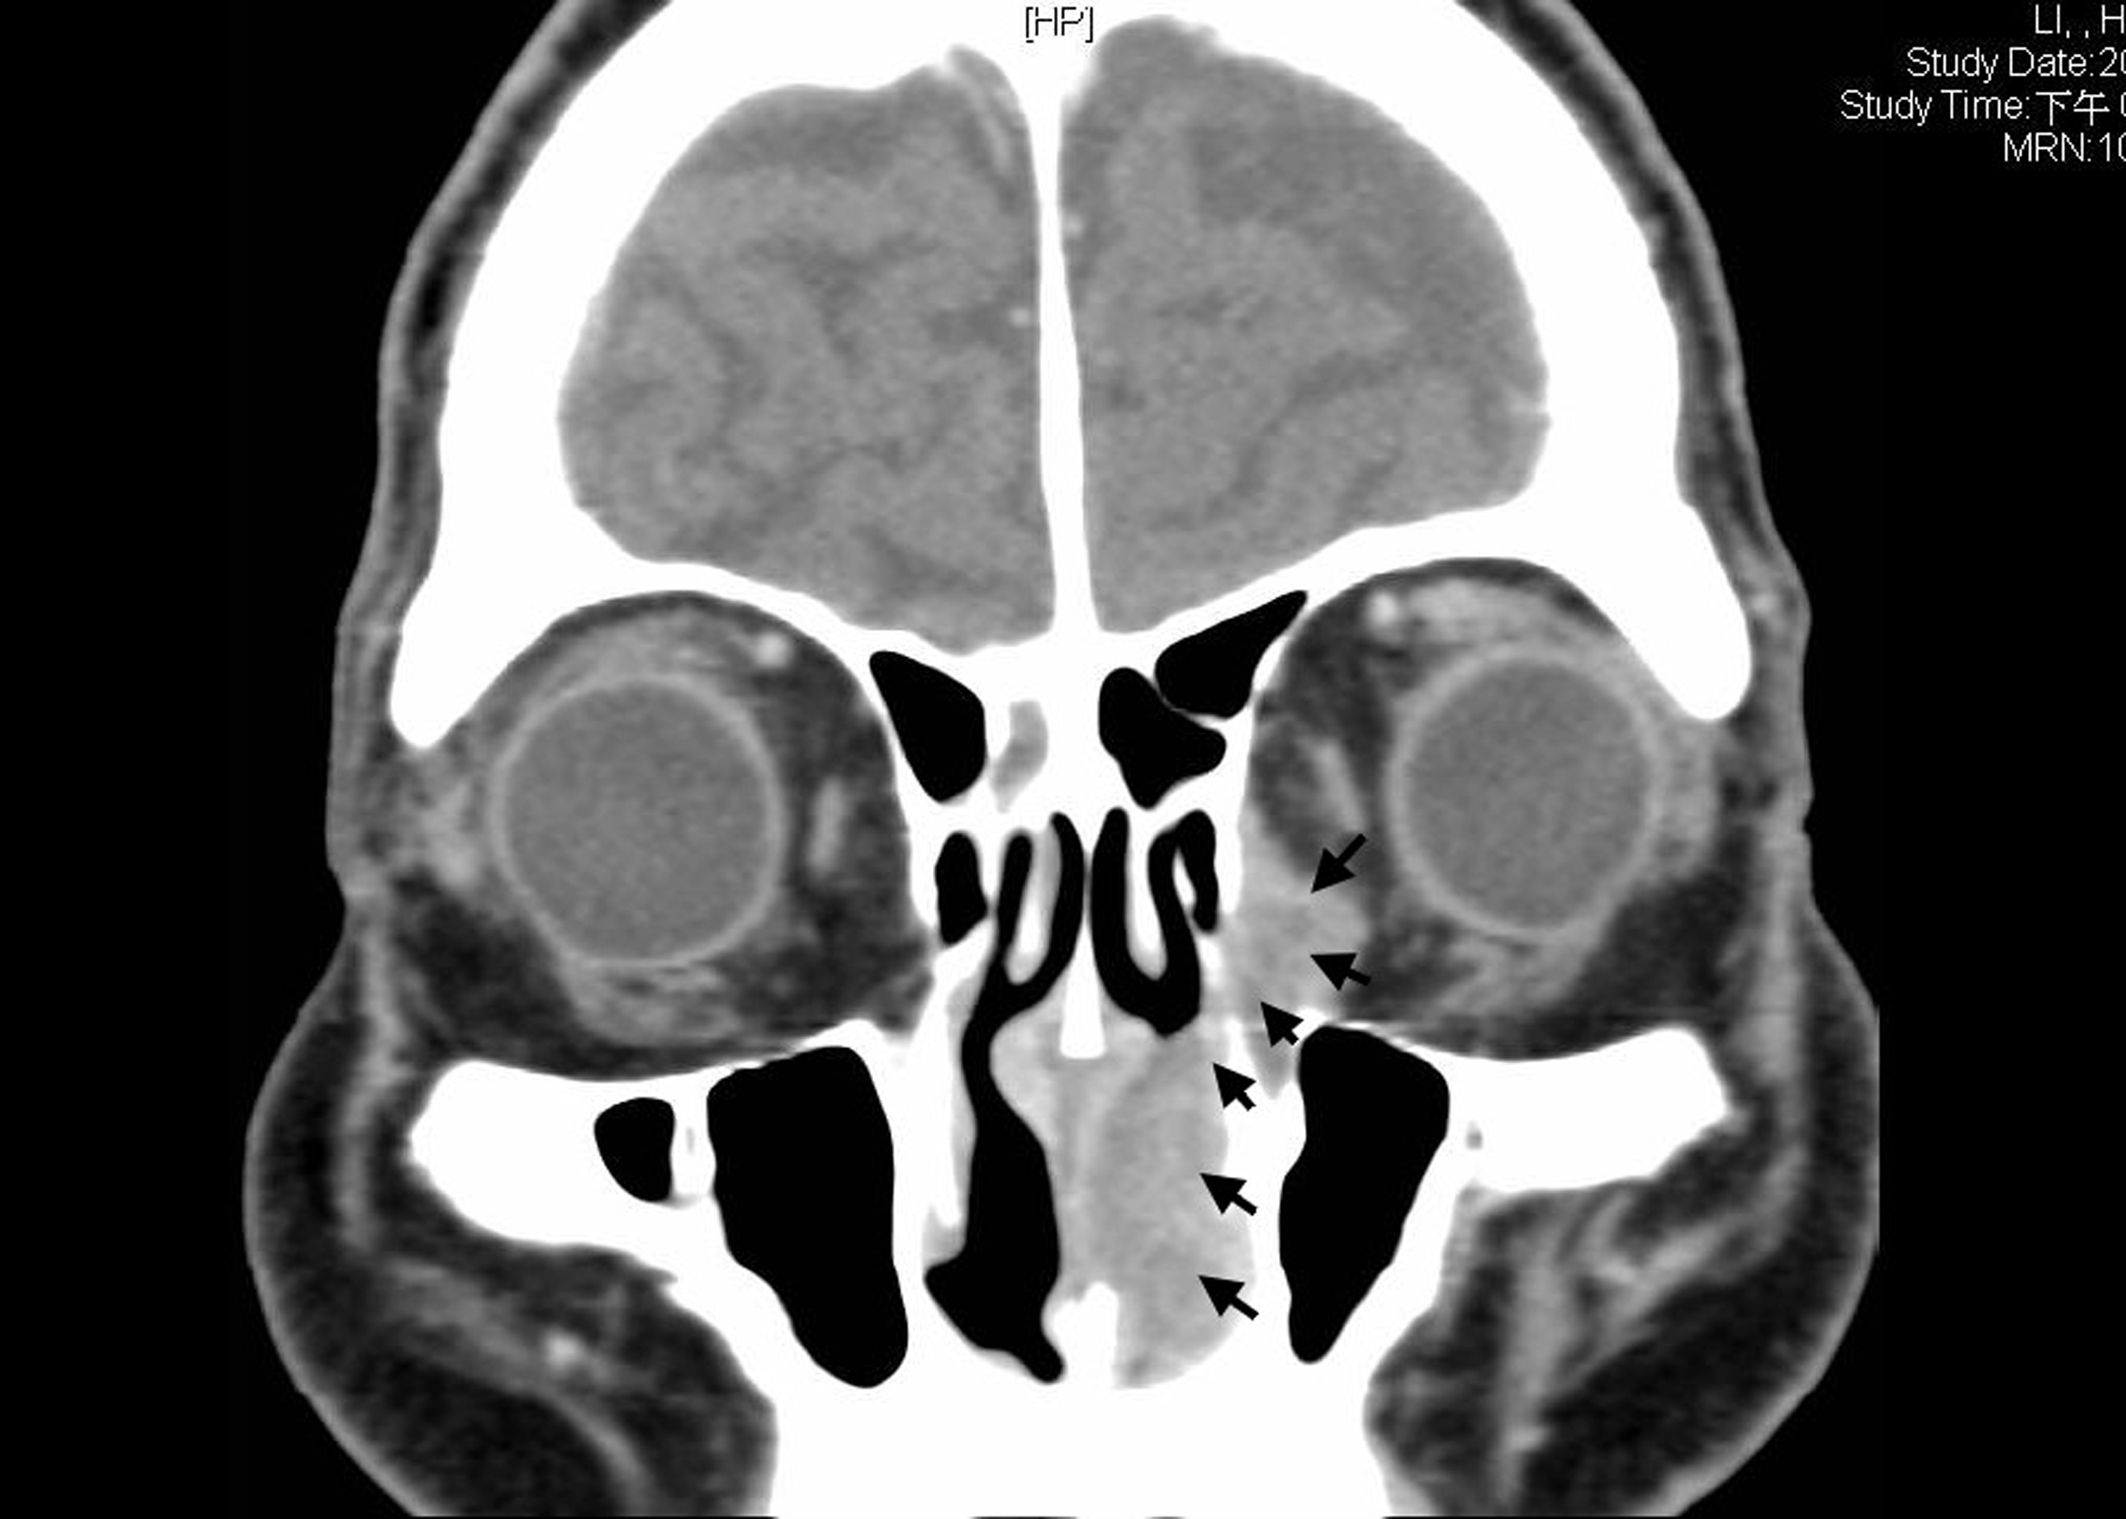

We here present a 78 year-old man with old stroke and under aspirin treatment presented with a 2-month history of nasal obstruction and epistaxis. He also developed epiphora and ocular swelling in recent 1 week in his left eye. Physical examination revealed left periorbital swelling, chemosis, lateral gaze impairment and a dark-colored mass in left nasal cavity. NLD obstruction was demonstrated by probing and irrigation. The nasal tumor was biopsied. Mucosal melanoma was diagnosed by identification of melanin in the tumor cells and positive staining with S-100. Contrast enhanced T1-weighted MRI demonstrated an enlarged hyperdense lesion in left nasal cavity (Fig. 1A, asterisk) and a hyperdense lesion in left medial aspect of orbit with involvement of preseptal space and retrobulbar fat (Fig. 1B, asterisk). Contrast-enhanced CT demonstrated a dumbbell-shaped tumor in left medial canthal region and nasal cavity, connected by the NLD (Fig. 2, arrowheads).

![]() Click for large image | Figure 2. Contrast-enhanced CT demonstrated a dumbbell-shaped tumor in left medial canthal region and nasal cavity, connected by the nasolacrimal duct (arrowheads). |

Regarding the symptoms of nasal melanoma, unilateral obstruction and epistaxis accounted for 85-100% of symptoms [3]. Concomitant ocular symptoms including epiphora, ocular swelling occurred infrequently unless direct involvement of orbit by the nasal tumor. Two theories were proposed about the development of simultaneous orbit and nasal cavity melanoma. One is direct spread or spread via the blood vessels from the nasal cavity or the paranasal sinuses into the orbit. The other is the tumor invades directly into the orbit by destructing lamina papyracea or orbital floor. The spread of tumor through the NLDs instead of destructing bony structure was rarely reported [4], but it was apparent from both the CT can and MRI in our patient.